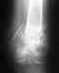

Здравствуйте. Около 3-х месяцев назад мы с женой попали в страшную аварию. Я слава богу уже восстановился а вот жена все еще нет. Она сломала себе бедро, точнее диафиз бедра, ей сделали операцию, совместили кость и 4 отломка пластиной и закрепили все на 8 шурупов. 2 месяца она пролежала дома в гипсе (гипс был вплоть до груди) и вот уже прошло более 3 недель как ей сняли гипс и сказали разрабатывать ногу.